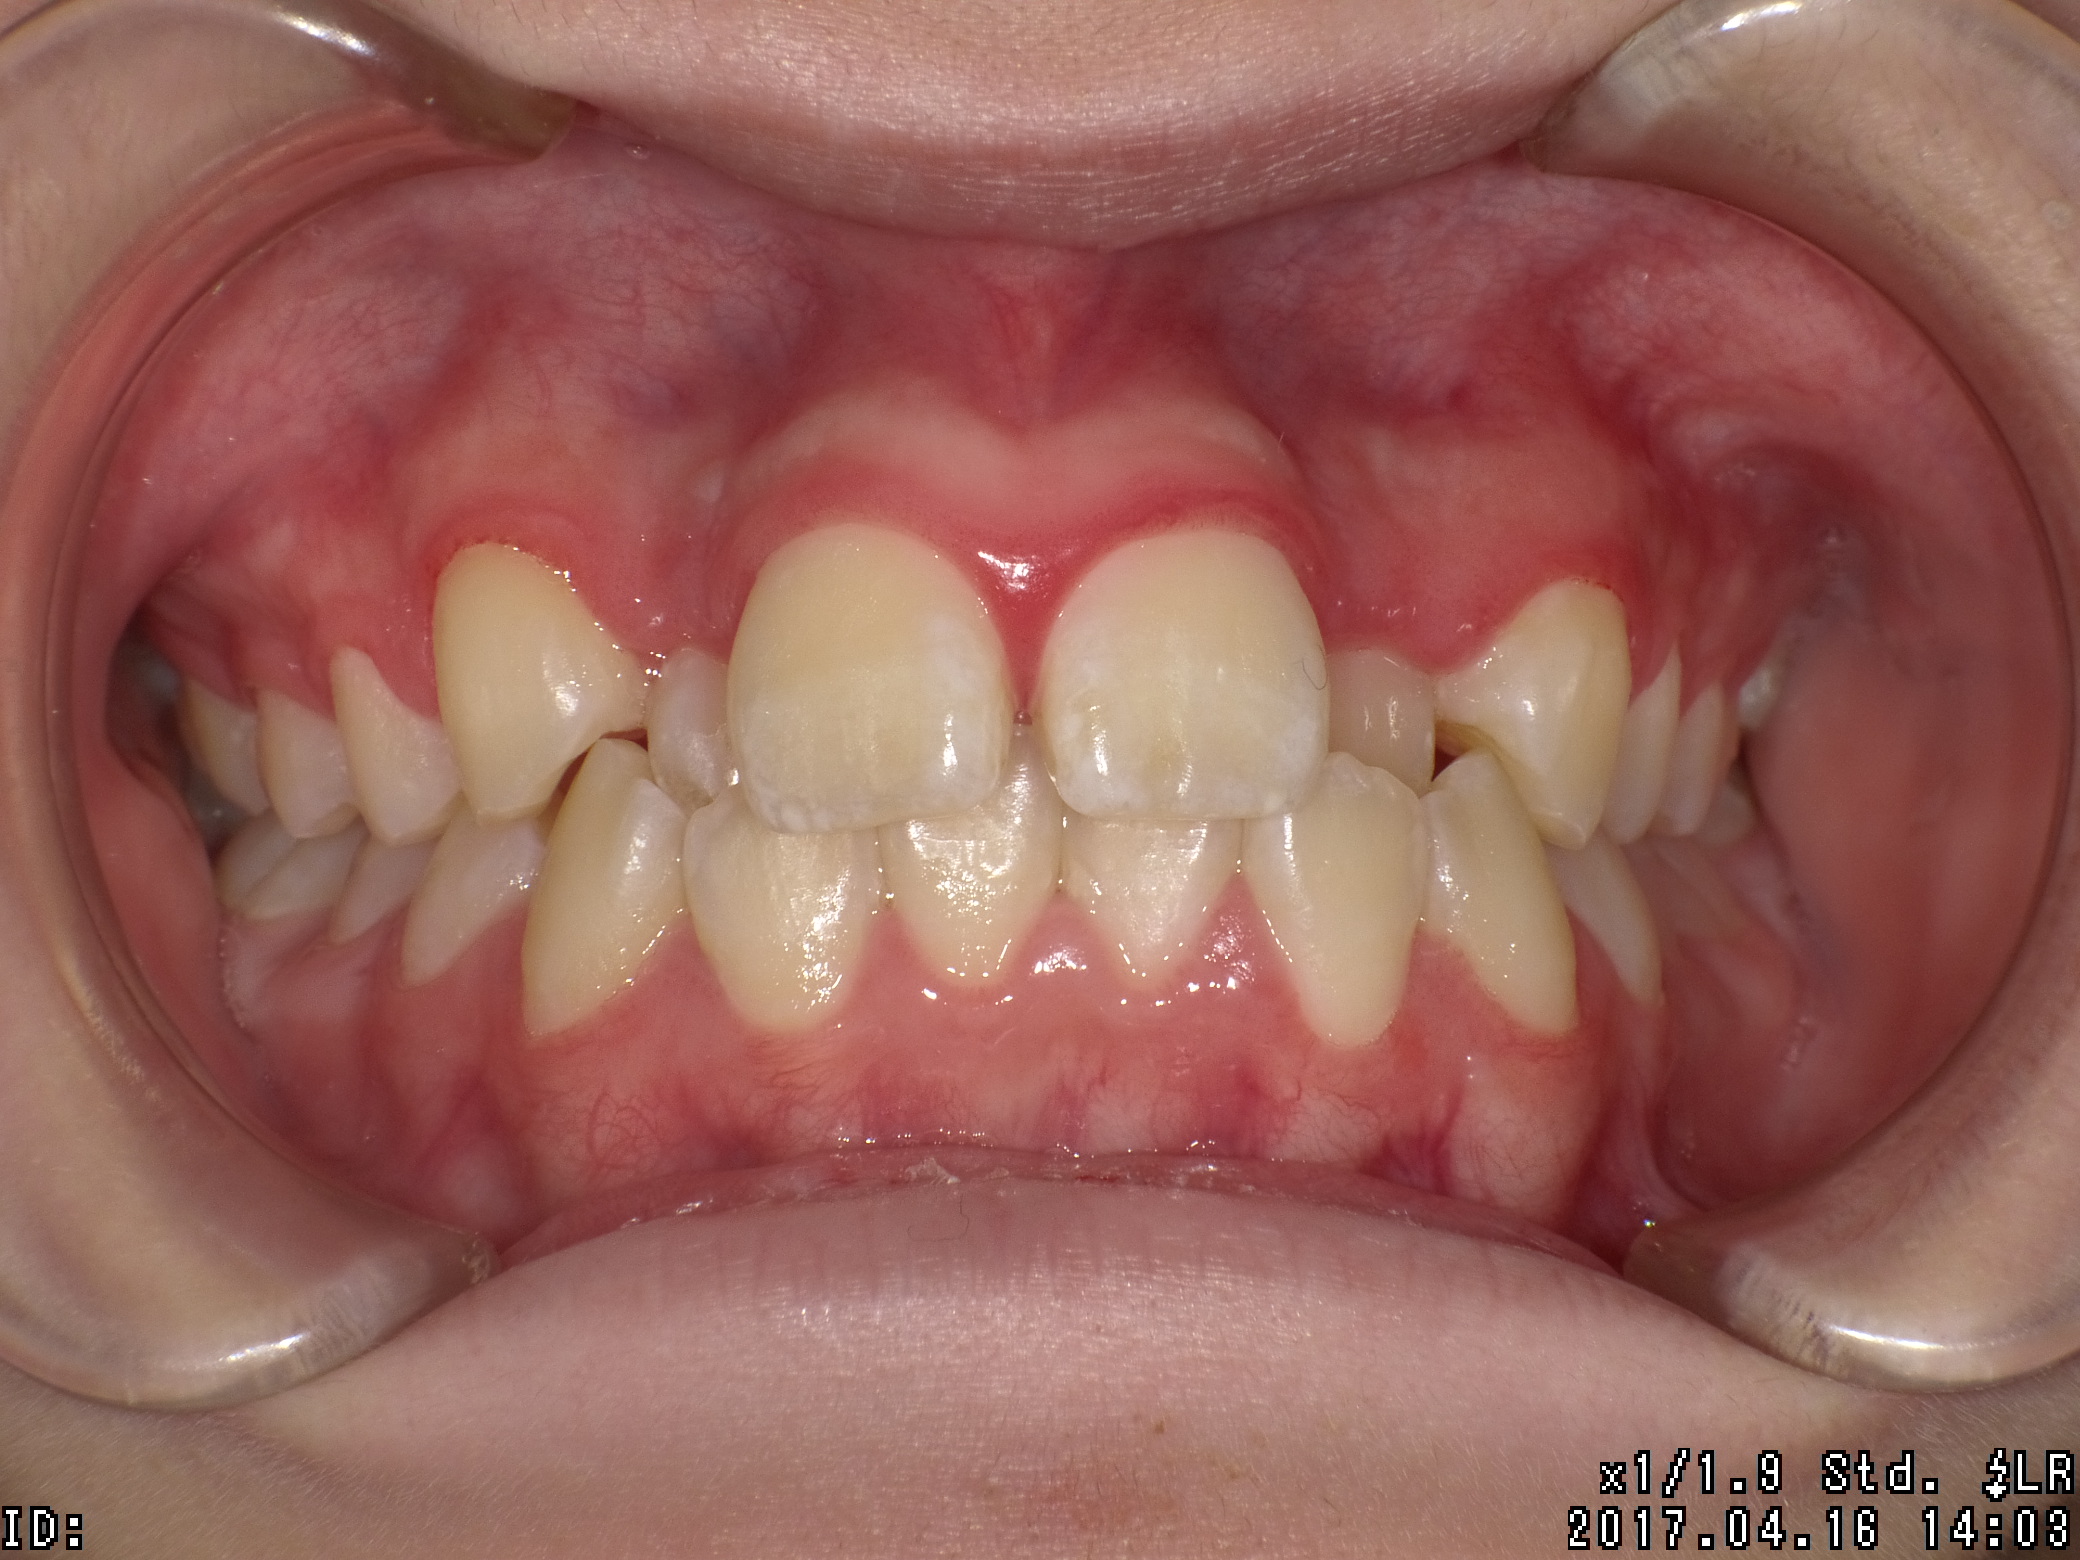

| 治療期間 | 2017年04月 〜2019年08月 |

|---|---|

| 治療費用 | 約700,000円 |

| 抜歯有無 | 抜歯有り |

| 矯正箇所 | 上顎・下顎 |

| 治療のリスク | 治療の過程で使用する針金やゴムにより、違和感や不快感を感じたり、口内炎になることがあります。 |